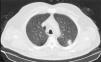

We report a 68-year-old man, smoker of more than 40 pack-years, who was seen in the ophthalmology clinic for a 20-day history of loss of sight in the right eye. Examination of the eye revealed bilateral venous thrombosis of the retina. Additional examinations were performed to rule out secondary systemic disease. Clinical laboratory, coagulation, serological and autoimmune examinations and computed tomography (CT) of the brain were performed; all results were negative. A chest X-ray was performed, revealing a nodule in the left upper lobe (LUL). Chest CT confirmed a 14mm spiculated nodule in the posterior region of the LUL, indicative of malignancy (Fig. 1), and a diagnosis of lung adenocarcinoma was confirmed by the pathology report. No pathological contrast uptake was found in any other sites on PET-CT.